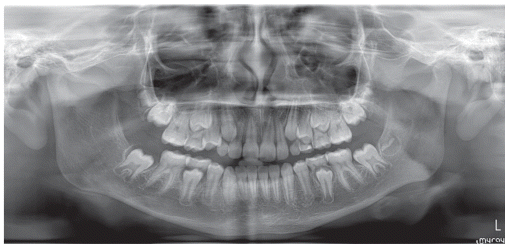

The patient was a growing female child who presented during early mixed dentition with an anterior crossbite associated with a deep overbite and a marked sagittal discrepancy (Figures 12–19). The initial clinical examination revealed a negative overjet, complete anterior deep bite, and a functional Class III occlusal pattern. Extraoral assessment showed a flattened facial profile, while cephalometric analysis confirmed a skeletal imbalance characterized by increased SNA and SNB values, an ANB of 0°, negative Withs appraisal, and significant dentoalveolar compensations, including proclination of both upper and lower incisors (Table 3). The vertical pattern was predominantly hypodivergent, suggesting a high risk of unfavorable mandibular growth progression if left untreated. Given the patient’s young age and growth potential, an early interceptive treatment was planned to use the AMCOP® TC appliance, with the aim of correcting the anterior crossbite, improving neuromuscular balance, and guiding sagittal and vertical development during growth. The appliance was worn nightly and for additional daytime hours, according to patient compliance.

After 18 months of treatment, a clear clinical improvement was observed. Intraoral examination demonstrated complete correction of the anterior crossbite, with establishment of a positive overjet and normalization of the anterior occlusal relationship. The deep bite was reduced, allowing more functional anterior guidance. Occlusal relationships improved toward a stable dental Class I, and the need for excessive dentoalveolar compensation was reduced. Cephalometric reassessment showed an overall improvement in sagittal relationships and incisor inclinations, with a trend toward normalization of the previously altered parameters. These findings indicate that early functional therapy with the AMCOP® TC appliance was effective in intercepting the developing Class III malocclusion, improving occlusal function, and potentially reducing the severity of future skeletal discrepancies (Table 4).